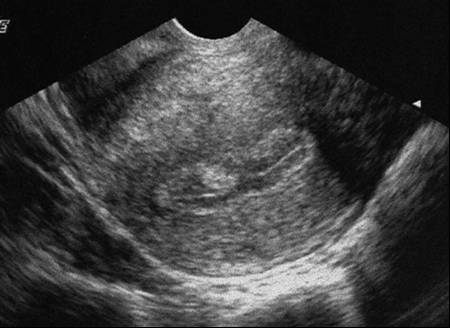

Polype endométrial hyperéchogène (Cliché : Dr. C. TALMANT)